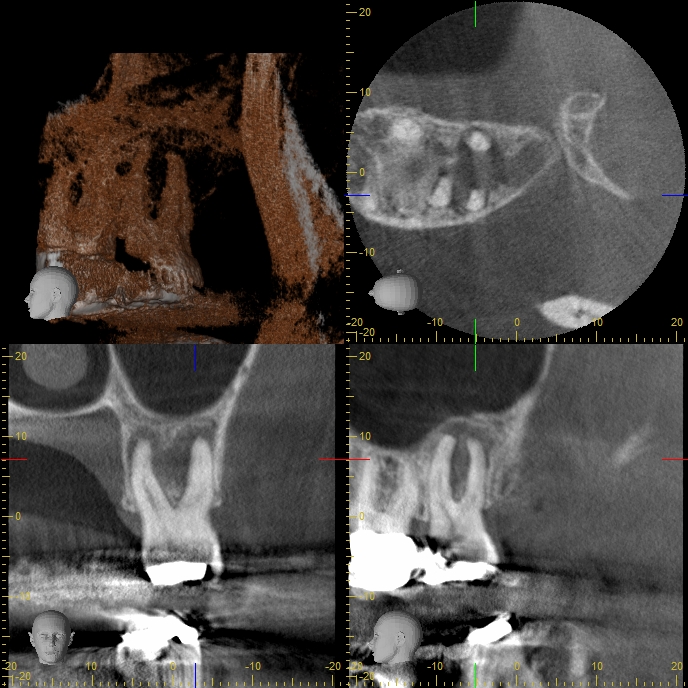

27AA Veröffentlicht 6. Mai 2014 am 688 × 688 in Massive apikale Aufhellung an Zahn 27 im Recall DVT Screenshot vor Endo